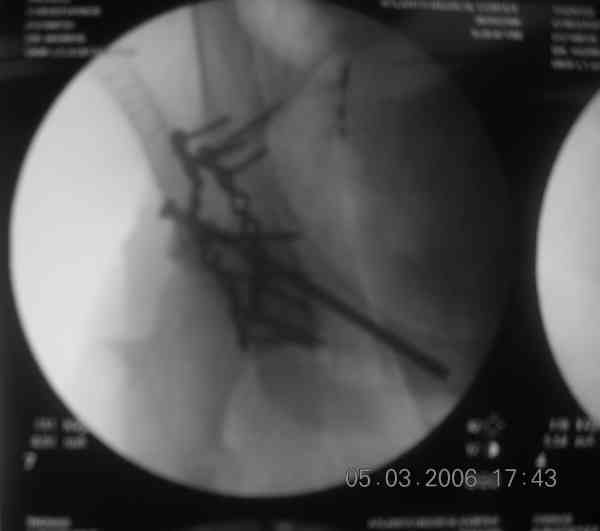

The 2nd example is of a motorcyclist with a transverse fracture-dislocation...he had a closed attempted reduction and placed in traction but the manipulative reduction was not concentric (not unusual for this injury pattern)...so the traction was adjusted to be just enough to disengage the head from the fracture (12#) until he could be cleared for surgery one day after injury...he was treated "urgently" then with a prone KL, clean the fracture, reduce and clamp it, screw it, support with a balanced plate, close, and enjoy...2-3hours, 400cc EBL, blah, blah, blah..

Here's a pic from the foot of the bed and you can see the clamp in the wound and the knee is extended so he must've had a tight rectus. The C-arm is rolled back to an obturator oblique image to reveal the anterior column...we put a slight outlet tilt to combine the images and give a better view of the anterior column...we can see the posterior column limb reduction in the wound, we can palpate the quadrilateral surface limb, and the image demonstrates the anterior column portion...you can adjust the tilt and rotation to image tangentially to the fracture plane if you'd like. We've inserted a 2mm K wire to site the starting point and aim/orientation for the drill and screw

Prone Imaging